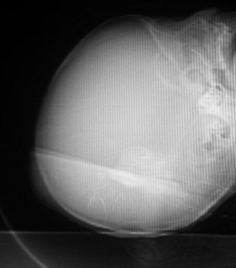

男,60天,发现头顶部囊性肿物2天。

轴扫没法说,还是看病人做冠扫吧!

考虑左侧顶骨皮样囊肿或表皮样囊肿,脑膜脑或脑膜膨出待排.建议冠扫